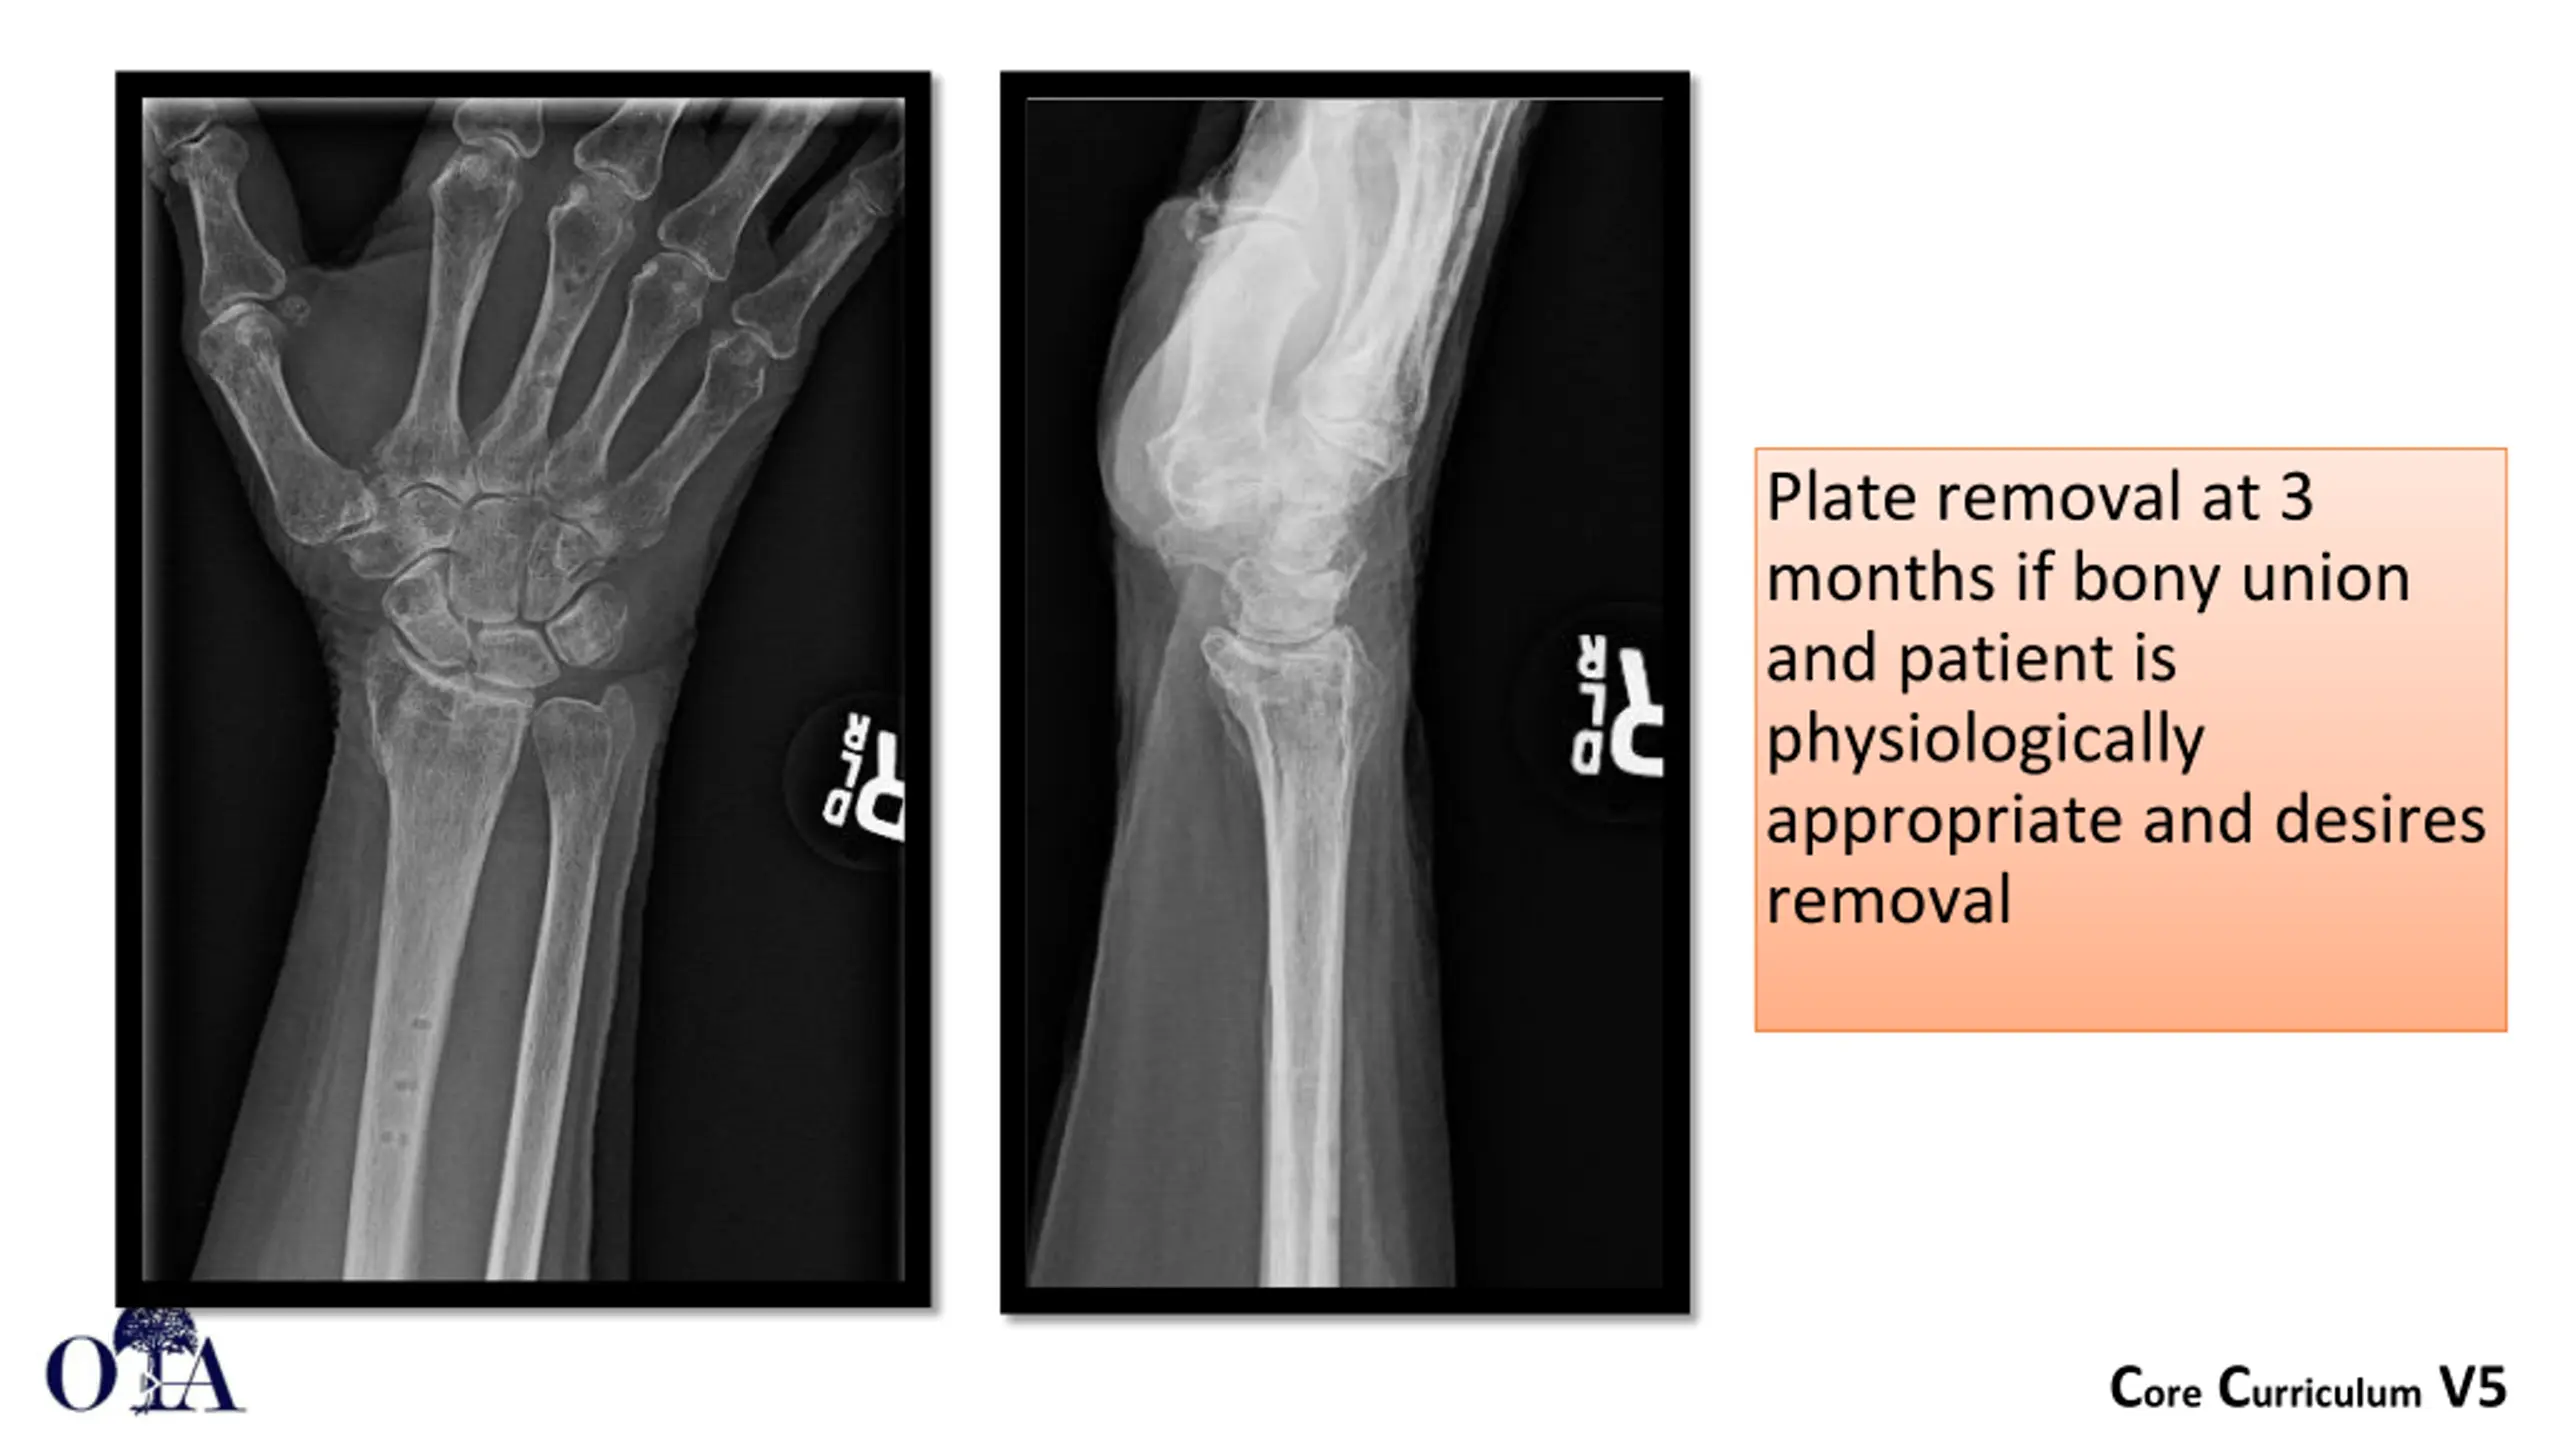

Distal Radius: Dorsal Spanning Plate Limited Incision localized fluoroscopically Centered between 2ndand 3rd metacarpal Dorsal aspect of the radius Deep exposure between 2nd and 3rdcompartments Superficial Radial Nerve at risk Plate slid under the extensor retinaculum which is never exposed Image courtesy of G. Moloney Core Curriculum V5

Plate can be placed on the 2nd or 3rd metacarpal 2nd metacarpal may assist in regaining radial height Core Curriculum V5

Plate can be attached to the metacarpal first and then used to regain length Core Curriculum V5

Plate removal at 3 months if bony union and patient is physiologically appropriate and desires removal Core Curriculum V5